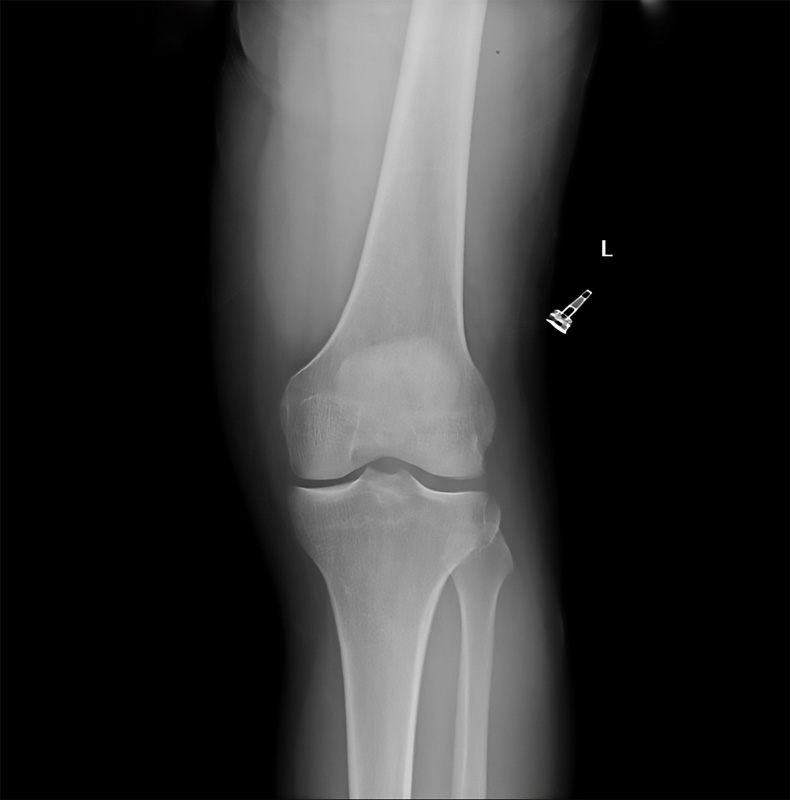

En 1879, Paul Segond describió una fractura-avulsión en la parte proximal externa de la tibia con la rotación interna forzada en rodillas cadavéricas humanas(2) debido a una banda fibrosa y resistente. Cien años después de la descripción de esta lesión, en 1979, se comenzó a asociar esta lesión con la presencia de inestabilidad en la rodilla(67).

Clásicamente, se ha considerado a la fractura de Segond un signo patognomónico de la lesión del LCA en la población adulta(68,69,70). La localización de la inserción tibial del LAL posterior al tubérculo de Gerdy(1,8,9,10,11,39,40) y la frecuente combinación con la lesión del LCA hacen que se haya relacionado la lesión de esta estructura con la fractura de Segond(9,27,28). La banda iliotibial(5,68,69), la zona central de la cápsula articular(6,67), el brazo anterior de la cabeza corta del bíceps femoral(70) y la banda anterior del LCL(5,71) también han sido propuestos como causantes de esta lesión(72)(Figura 4).

Figura 4. Avulsión ósea en zona lateral de tibia proximal (fractura de Segond).